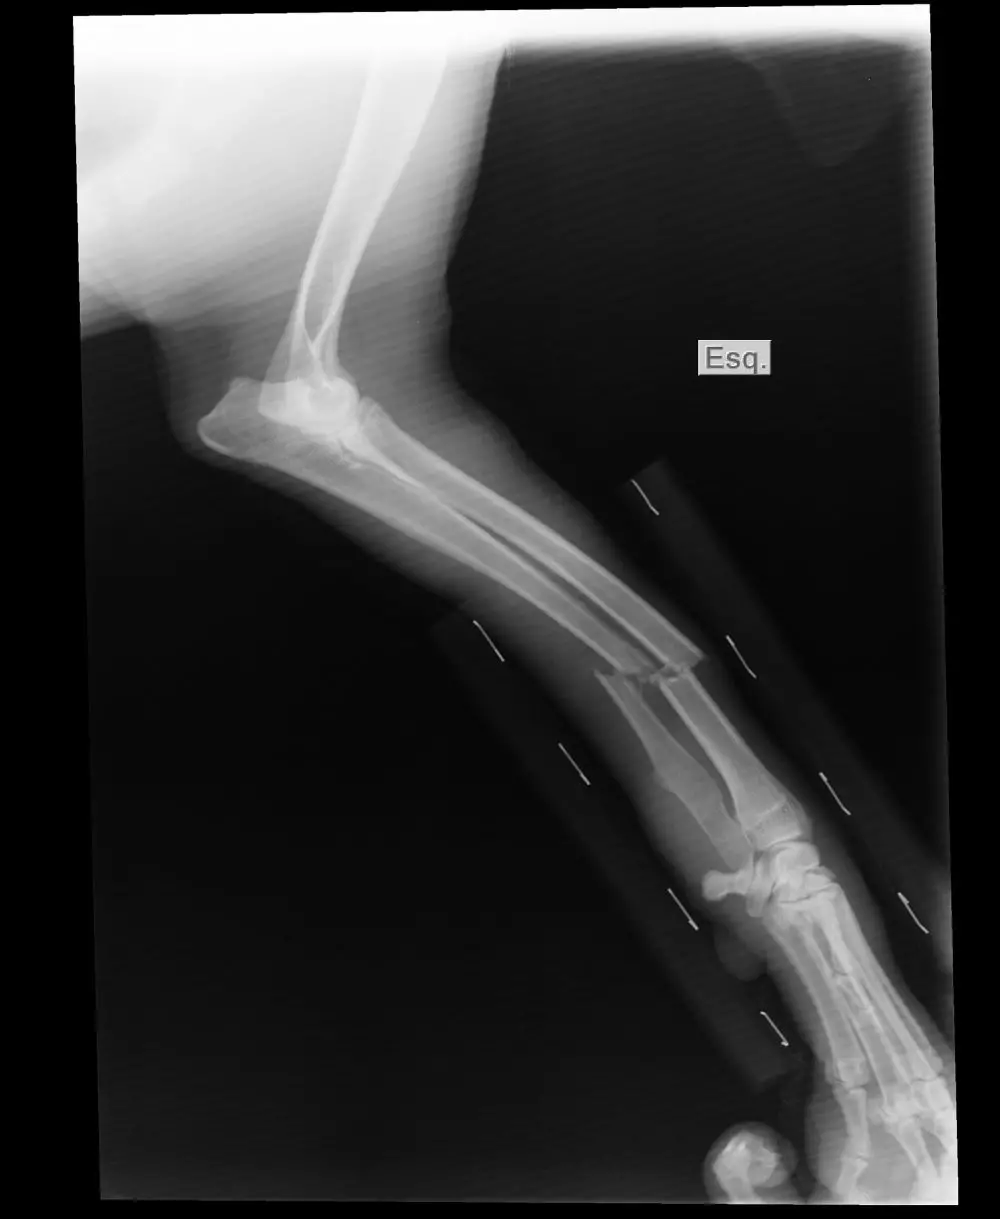

2. Deformitas atau perubahan bentuk tulang.

Deformitas pada patah tulang adalah perubahan bentuk atau posisi normal tulang akibat patah. Deformitas bisa terlihat sebagai pergeseran tulang yang tidak normal, misalnya tulang yang miring atau bergeser keluar dari posisi yang seharusnya. Deformitas bisa terlihat jelas pada kasus patah tulang yang parah, seperti patah tulang terbuka atau patah tulang yang tidak teratasi dengan baik.

Deformitas pada patah tulang dapat menyebabkan gangguan fungsi tulang dan jaringan sekitarnya, serta dapat meningkatkan risiko komplikasi seperti gangguan peredaran darah atau kerusakan pada saraf di sekitar area patah tulang. Oleh karena itu, penanganan deformitas pada patah tulang perlu dilakukan secara hati-hati dan sesegera mungkin oleh tenaga medis yang berpengalaman.